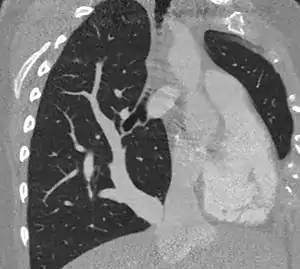

| Scimitar syndrome chest CT | |

The diagnosis is made by transthoracic or transesophageal echocardiography, angiography, and more recently by CT angiography or MR Angiography.